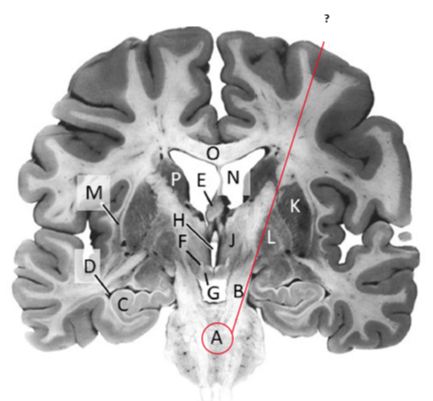

Name this and state its function.

Corpus Callosum.

Name and state its function.

Lateral ventricles.

Hippocampus.

Thalamus.

Third ventricle.

Caudate nucleus.

Name this ,state its function and the name of the structures closely associated with it.

Putamen.

Name this, state its function and its components[4 marks].

Globus Pallidus.

Components:

Crus Cerebri.

Name this and state its function. Also, state all 3 fibres involved.

Basilar pons.

Claustrum.

Name.

Temporal horn of lateral ventricle.

Name this, state its function and consequence of lesion in this area.

Fornix.

Transmits Theta waves aswell.

Lesion: anterograde amnesia.

Name this and state its function. And what tract is involved?

Mamillary bodies.